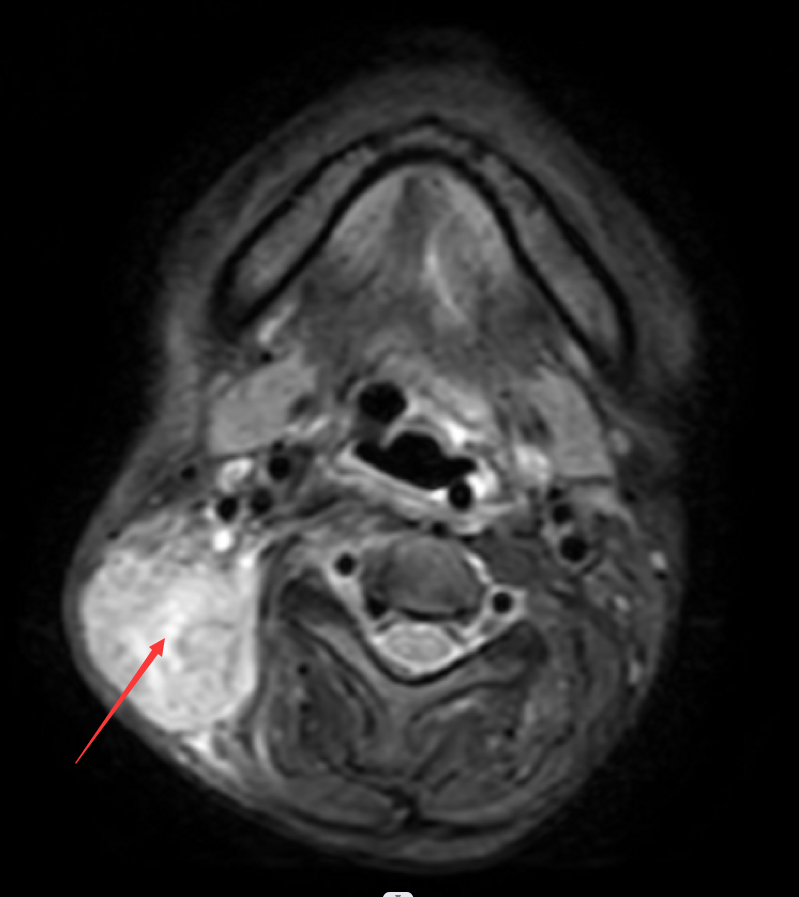

·2020-10-03再次住院,因患者肺部感染严重,暂无法化疗。右颈部淋巴结转移瘤仍较大,局部肿痛明显,故2020-10-20至2020-10-22继续行右侧颈部淋巴结转移瘤第二次射波刀治疗。

(射波刀治疗后10天,患者右颈部肿瘤已较前明显缩小,局部疼痛明显减轻。射波刀治疗后2月复查MRI提示右颈部淋巴结已消失)。进展后继续化疗加中药巩固治疗,小萍整个治疗过程,均长期配合中医药辨证治疗。此阶段的小萍情况明显好转,可生活自理,住院期间无需陪人照料,饮食、睡眠基本恢复正常。颈部肿块消失,疼痛明显缓解,无需止痛药治疗。

2020年10月22日射波刀治疗前